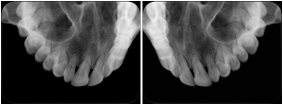

2. A patient requests cosmetic surgery to enhance their facial appearance. The case requires consultation between an orthodontist in New York and an oral surgeon in California. The cephalometric series of 2D projections constructed from the volumetric CT data that is used for the discussion is arranged by a Structured Display for transfer between the two practitioners.

Cephalometric Series Structured Display

Figure OO-2. Cephalometric Series Structured Display